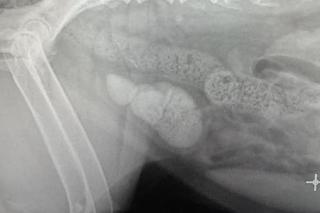

Rutynowe badanie RTG 9-letniej suczki „Gai” zszokowało weterynarzy z Lecznicy Ada w Przemyślu. Psinka miała w pęcherzu kilkaset kamieni. Od wielkich niczym kurze jaja, do malutkich jak koraliki. W każdej chwili pęcherz mógł pęknąć niczym rozdęty do granic możliwości balon. Decyzja była jedna i natychmiastowa - operacja. Co spowodowała taki stan u psa?

- Kamienie w pęcherzu moczowych to częsta przypadłość psów i kotów. W wyniku infekcji układu moczowego, nieprawidłowego karmienia, nadwagi, chorób metabolicznych tworzą się kryształki, które z czasem tworzą kamienie. Jeżeli w porę nie wykryjemy tej przypadłości, to może skończyć się to dużym bólem, zatrzymaniem oddawania moczu, uszkodzeniem nerek albo śmiercią. Tylko regularne badanie moczu co 6-12 miesięcy może w porę wykryć nieprawidłowości w jego składzie. Wtedy wystarcza leki i zmiana trybu życia. W przypadku tak obfitych kamieni jak u “Gai”, jednym ratunkiem była operacja. Co może cię zaniepokoić? Nietrzymanie moczu, posikiwanie, kropelkowanie, czyli oddawanie niewielkich ilości moczu, krwiomocz, wokalizacja przy oddawaniu moczu, polidypsja, czyli zwiększone pragnienie, wylizywanie brzucha i okolicy ujścia cewki moczowej, ogólne złe samopoczucie. Wtedy zgłoś się do lekarza natychmiast - instruowała weterynarz Radosław Fedaczynski.